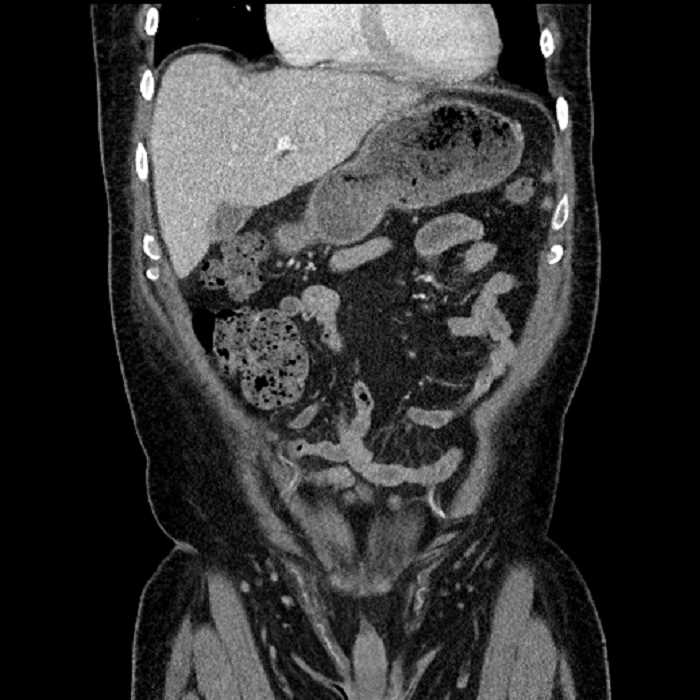

• Mild mural thickening of a segment of the sigmoid colon with adjacent fat stranding and a 1.5 cm fluid and gas collection along the tip of an inflamed diverticulum

• Loss of the normal fat plane between this collection and adjacent loops of small bowel, which demonstrate mural thickening

Acute sigmoid diverticulitis complicated by a small contained perforation and a large abscess in the right hepatic lobe. Additional small subcapsular abscesses along the anterior margin of the left hepatic lobe.

Additionally, loss of the normal fat plane between the peridiverticular collection and adjacent thickened loops of small bowel raises the potential for an enterocolonic fistula.

Hepatic abscess showing the double target sign with low density internally surrounded by a thin inner enhancing rim (red arrow) and ill-defined outer low density rim (yellow arrow). Blue arrow indicates an internal septation. Red arrows: additional smaller subcapsular abscesses. Red arrow: focal contained perforation associated with diverticulitis.